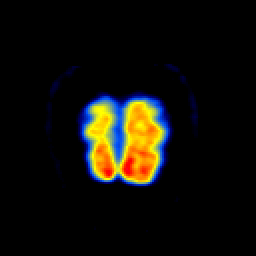

3. PET(正电子发射断层扫描)

原理:

- 注射正电子核素标记药物(¹⁸F-FDG)

- 正电子湮灭产生γ光子对(511keV)

- 符合探测技术定位代谢热点

- SUV值定量代谢活性

关键技术:

- 时间飞行技术(TOF)提高分辨率

- PET/CT融合(解剖+代谢)

- 新型示踪剂(PSMA前列腺癌、DOTATATE神经内分泌瘤)

优势:

- 分子水平功能成像

- 全身肿瘤筛查

- 疗效评估(治疗后代谢变化早于形态学)

局限:

- 空间分辨率低(4-5mm)

- 价格昂贵(单次约万元)

- 需禁食准备(控制血糖)

临床应用:

- 肿瘤分期(NSCLC纵隔淋巴结评估)

- 阿尔茨海默病(β淀粉样蛋白显像)

- 心肌存活评估